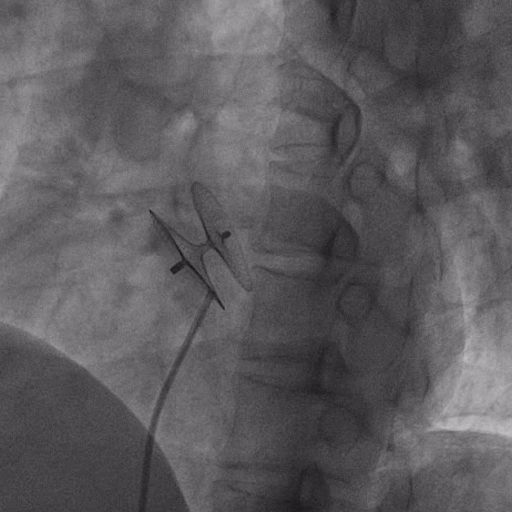

在獲得患者同意后,1月12日,尚福軍主任為患者進(jìn)行了PFO封堵術(shù)。術(shù)中造影可見封堵器殘余漏,尚福軍主任用精湛的技藝,順利通過封堵器殘余漏裂縫,將右心導(dǎo)管從右房送入左房,且順利到達(dá)肺靜脈;遂行卵圓孔未閉封堵術(shù)后殘余漏再次封堵;且完美釋放PFO封堵器,可見兩封堵器呈“馬蹄蓮”狀,再次術(shù)中造影未見殘余漏。

術(shù)后,小鞏生命體征平穩(wěn)。相關(guān)檢查顯示正常,且術(shù)后完善心臟彩超及發(fā)泡試驗(yàn),可見封堵器位置良好,未見右向左分流,發(fā)泡試驗(yàn)陰性。